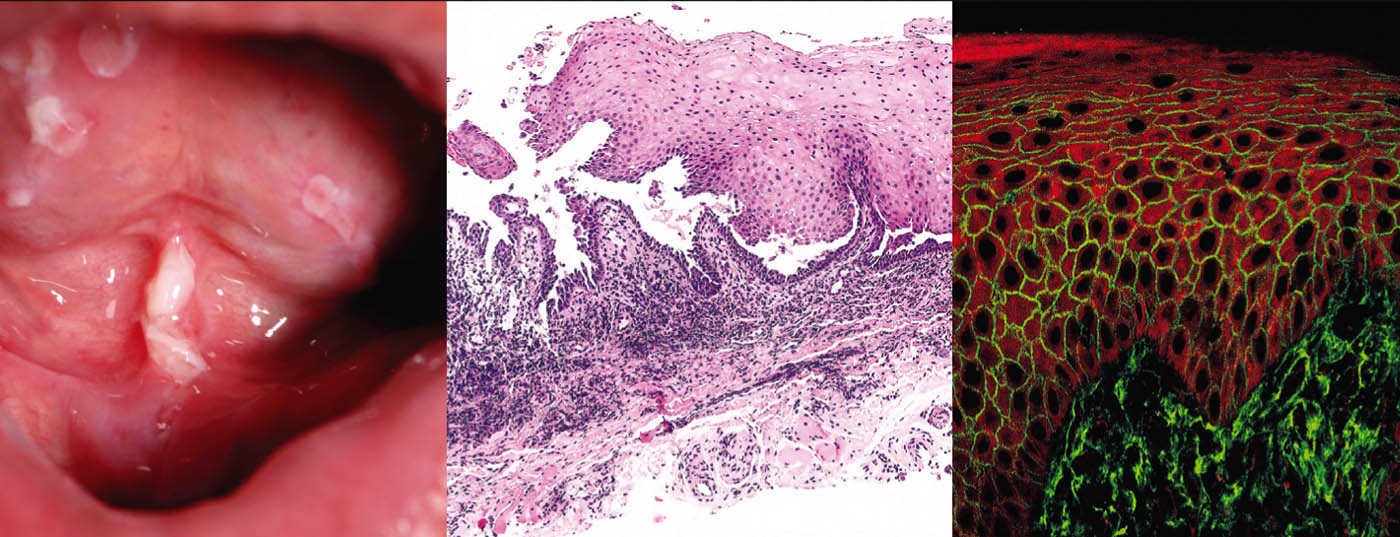

Bullöse Autoimmundermatosen stellen eine heterogene Gruppe von seltenen, teils schweren Autoimmunerkrankungen dar, zu welchen die Pemphigus- und Pemphigoid-Erkrankungen, die Epidermolysis bullosa acquisita und die Dermatitis herpetiformis Duhring zählen. Gemeinsames Charakteristikum der bullösen Autoimmundermatosen – mit Ausnahme des M. Duhring – sind Autoantikörper, welche gegen Strukturproteine der Haut und Schleimhäute gerichtet und für einen Verlust der kutanen Integrität verantwortlich sind [1].